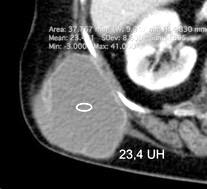

Hemorrágica………….30-70 UH

Extravasación iv. con sangrado activo……….>90 UH

“Simpático”………….,,,,<15 UH

Durso AM et al. Penetrating Thoracic Injury. Radiol Clin N Am 2015.

Urogénico……………….< 15 UH

Entérico.. ………………+/- 15UH

Biliar, Quiloso……………..<0 UH

Abramowitz1 Y et al. Pleural Effusion: Characterization with CT Attenuation Values and CT Appearance .AJR 2008